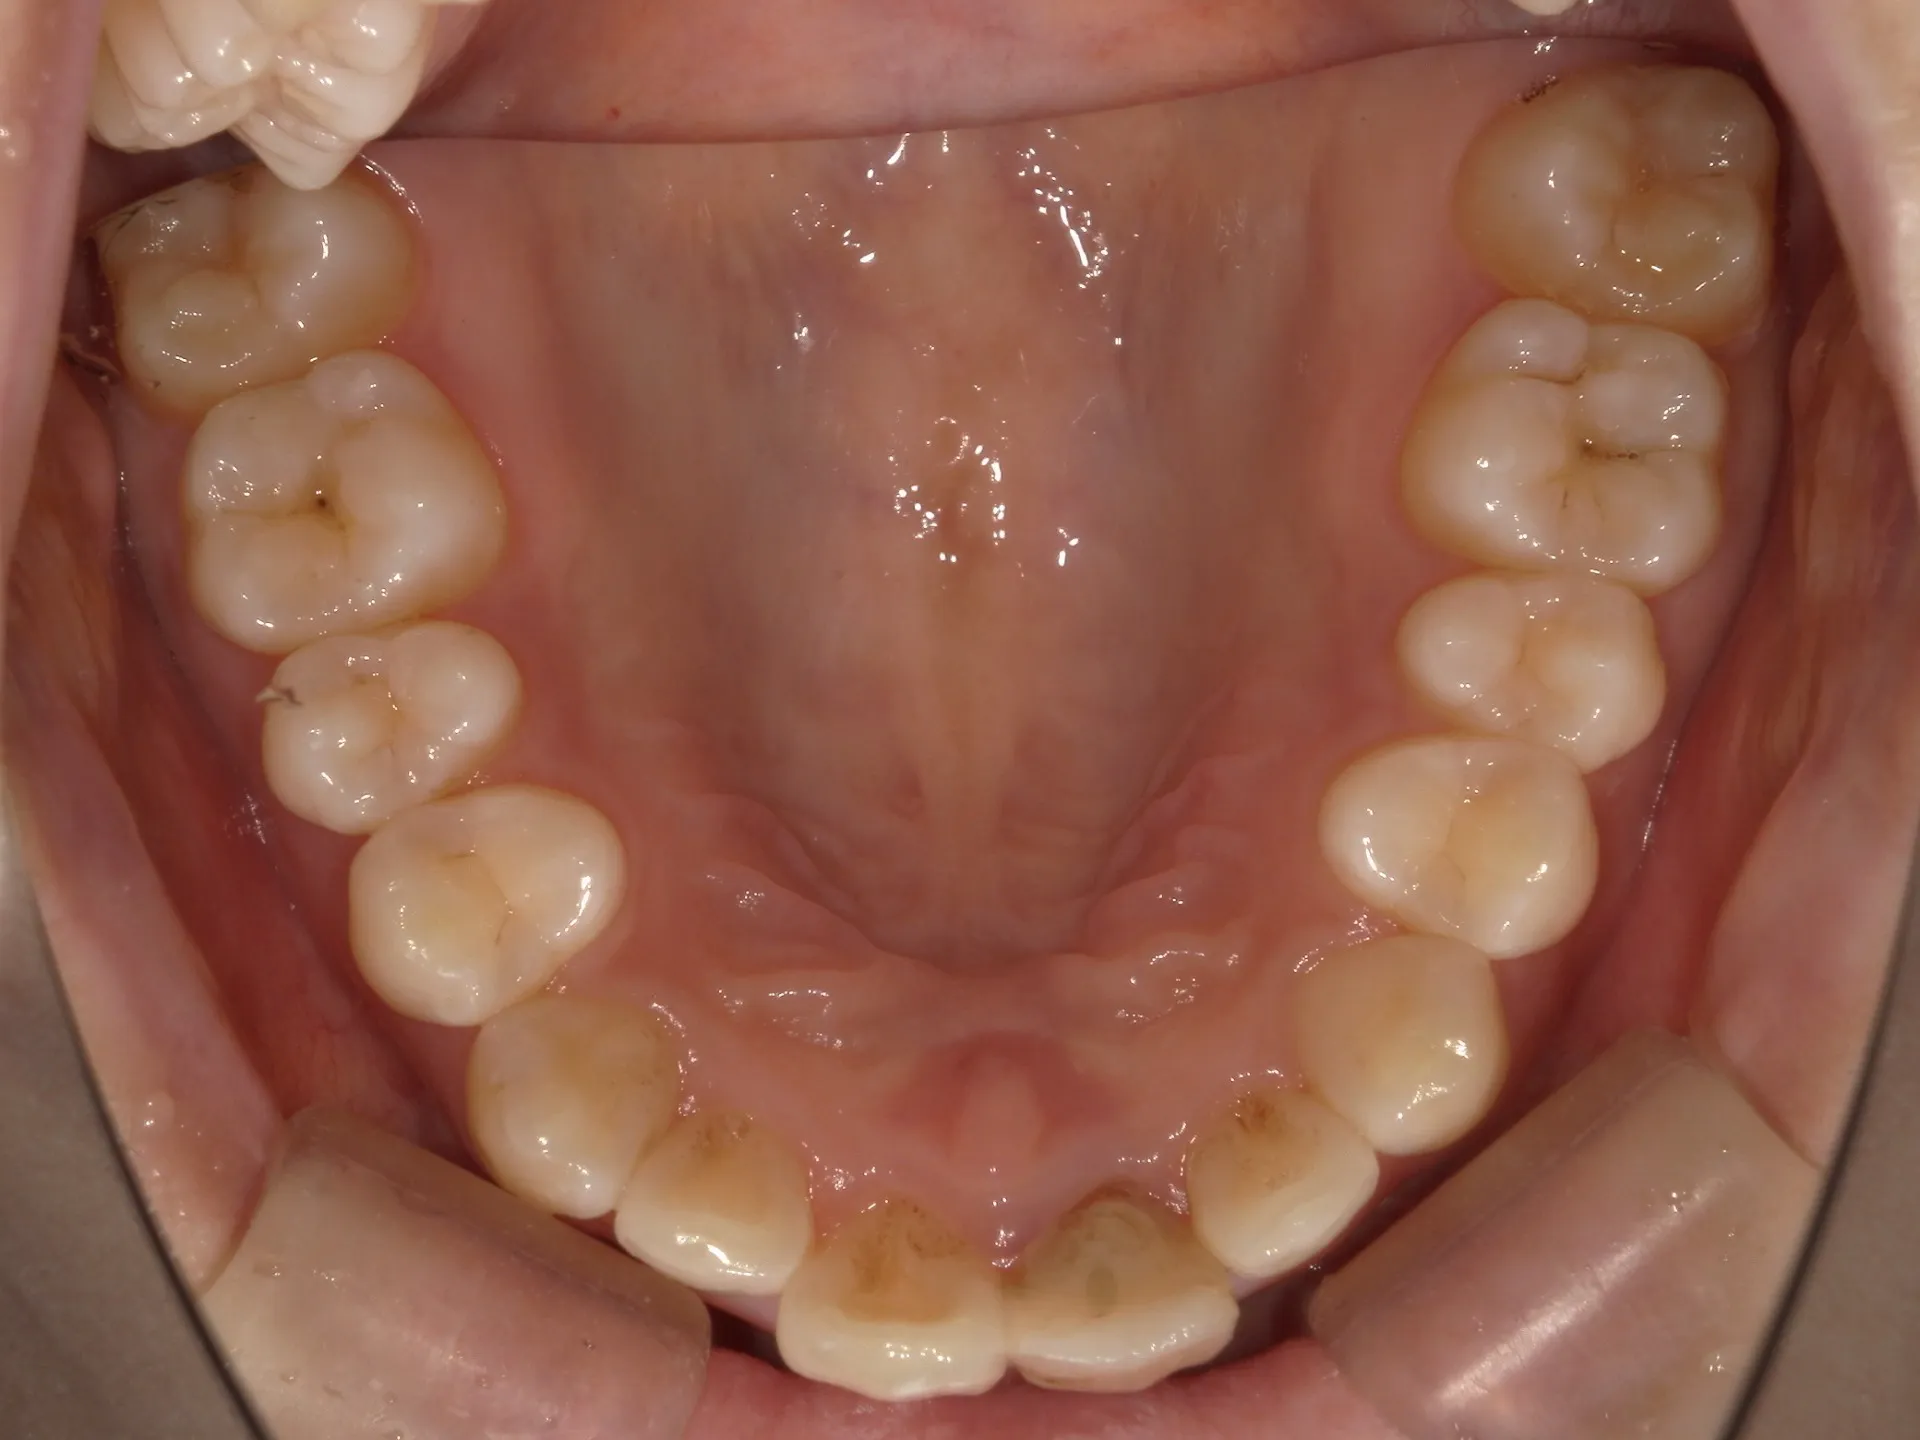

大きく飛び出してしまった前歯の矯正と変色の治療を希望された症例をご紹介いたします。